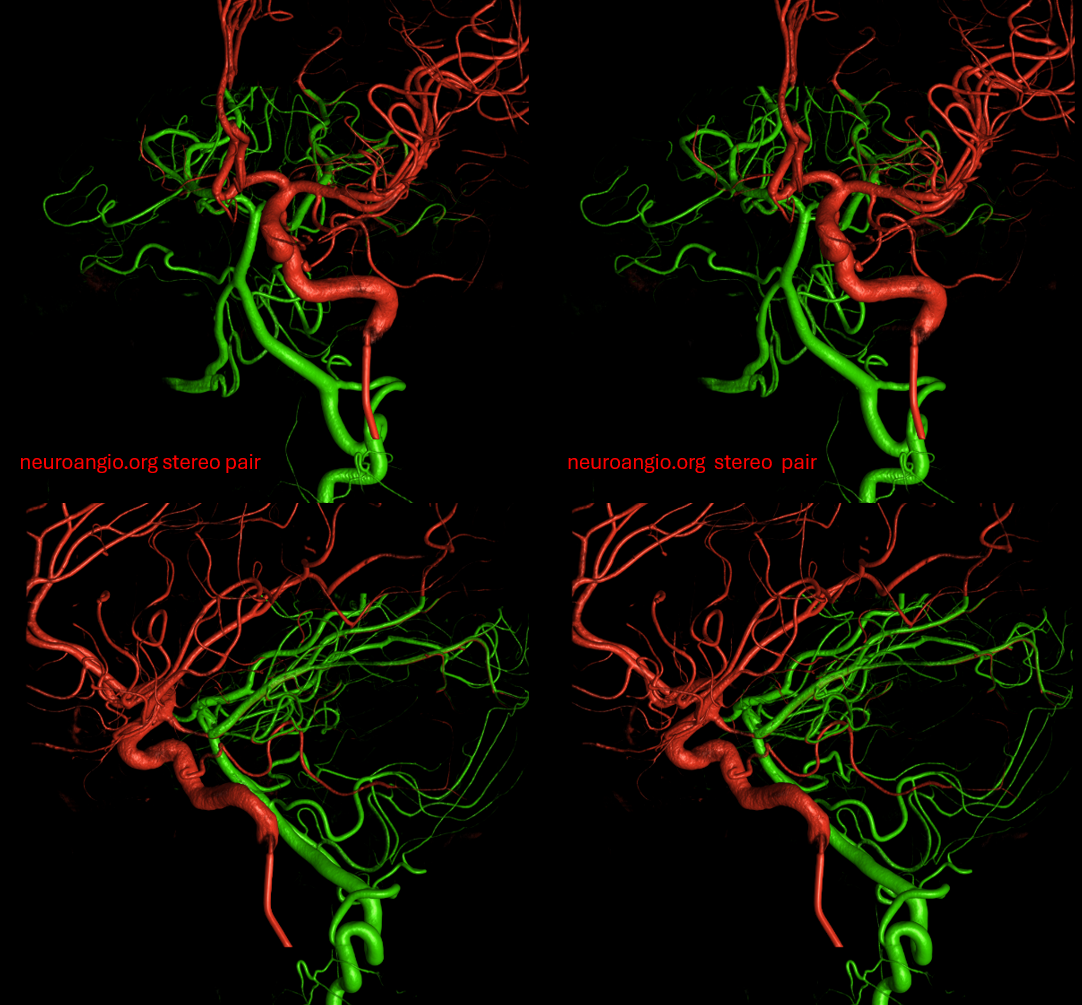

Now, for one of the most amazing stereos on the website:

The indispensable STEREO pair